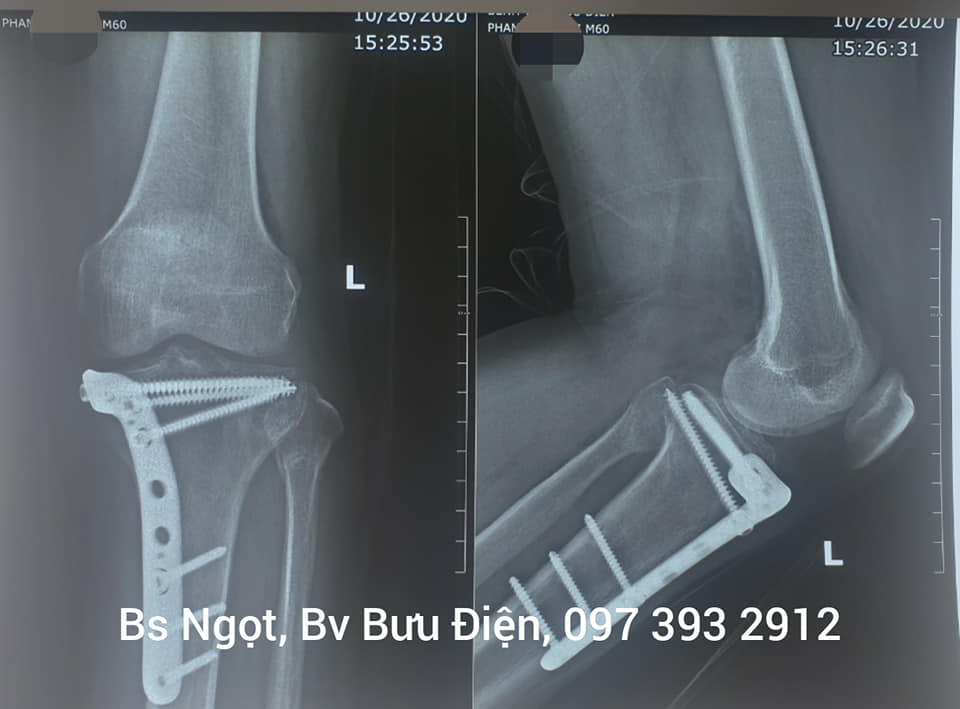

5.1. Tình huống bệnh nhân và chẩn đoán ban đầu

Bệnh nhân N.V.T, nam, 45 tuổi, gặp tai nạn giao thông dẫn đến đa chấn thương, trong đó nặng nhất là tổn thương phức hợp khớp gối và gãy xương mác. Sau phẫu thuật tái tạo tại bệnh viện tuyến trung ương, bệnh nhân đối mặt với tình trạng đau dai dẳng, cứng khớp, và hạn chế vận động nghiêm trọng (gối chỉ gập được 60 độ), ảnh hưởng đến khả năng đi lại và quay trở lại công việc.

5.2. Quy trình can thiệp và giải pháp điều trị chuyên biệt

Bác Sỹ Xương Khớp tiếp nhận bệnh nhân T. sau 3 tháng phẫu thuật. Phác đồ điều trị được thiết kế chuyên biệt, kéo dài 6 tháng, bao gồm:

- Giai đoạn 1 (Kiểm soát đau và giảm sưng): Sử dụng phương pháp châm cứu điện kết hợp liệu pháp nhiệt lạnh, giảm thiểu việc dùng thuốc giảm đau đường uống.

- Giai đoạn 2 (Phục hồi biên độ): Áp dụng các kỹ thuật vận động thụ động và chủ động tăng tiến, kết hợp xoa bóp bấm huyệt chuyên sâu để làm mềm mô sẹo và giải phóng sự co cứng cơ.

- Giai đoạn 3 (Tăng cường sức mạnh): Tập trung vào các bài tập kháng lực để củng cố cơ tứ đầu đùi và cơ gân kheo, đồng thời cải thiện khả năng giữ thăng bằng.

5.3. Kết quả đạt được và kinh nghiệm rút ra

Sau 6 tháng tuân thủ phác đồ, biên độ gập gối của bệnh nhân T. đã đạt 120 độ, giảm đau hơn 80%, và có thể đi lại, leo cầu thang gần như bình thường mà không cần dụng cụ hỗ trợ. Bệnh nhân đã quay trở lại làm việc và duy trì thói quen tập luyện hàng ngày theo hướng dẫn. Case study này nhấn mạnh rằng, việc phục hồi chức năng là một quá trình kiên trì và phải được dẫn dắt bởi chuyên gia có kinh nghiệm sâu rộng về hệ cơ xương khớp.